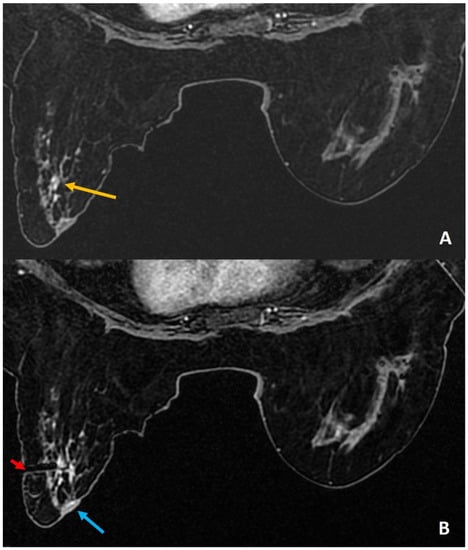

Figure 12.

(A). MIP image from staging scan of a woman with diagnosed left breast cancer (red asterisk) showed indeterminate lesion in the right breast (yellow arrow). (B). In absence of definite sonographic correlate, MRI-guided biopsy was arranged. The target was noted outside the grid compression (yellow arrow). (C). A free-hand direct insertion of the guide shows the tip of the obturator (red arrow) exactly within the target lesion (yellow arrow). The histology returned as normal breast tissue that was considered discordant. (D). Retrospective review of the post biopsy image showed the target lesion (yellow arrow) along the medial aspect of the hematoma (blue arrow). Possibility of accidental partial withdrawal of the needle during the vacuum procedure was considered, thus missing the target completely. This was communicated with the surgeon and excision biopsy was recommended in view of radiology–pathology discordance. Final surgical histology was reported as 7-mm invasive ductal carcinoma.